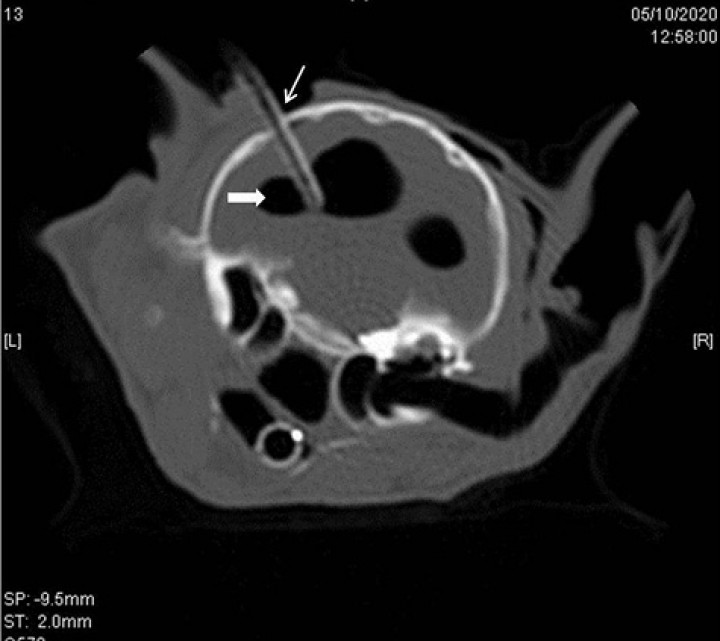

<p>Reformateo dorsal en ventana de hueso en el que se muestra que la lesión intracraneal, hipoatenuante, de márgenes bien definidos y redondeados, de densidad aire (probablemente ventrículo lateral izquierdo) (flecha sólida) comunica con el espacio extradural (flecha amarilla) mediante una fístula (flecha blanca). Además, se observa enfisema en los tejidos blandos del mismo lado (asterisco).</p>

Reformateo dorsal en ventana de hueso en el que se muestra que la lesión intracraneal, hipoatenuante, de márgenes bien definidos y redondeados, de densidad aire (probablemente ventrículo lateral izquierdo) (flecha sólida) comunica con el espacio extradural (flecha amarilla) mediante una fístula (flecha blanca). Además, se observa enfisema en los tejidos blandos del mismo lado (asterisco).

El aire acumulado en las distintas zonas ha entrado a través de una fístula (Fig. 3) y se ha instaurado un gradiente de presión negativo hacia la cavidad craneal situándose probablemente en los ventrículos laterales, provocando un gran aumento del tamaño de los mismos y adoptando una forma redondeada.

En nuestro caso, la entrada de aire hacia la cavidad craneal ocurrió a través del seno frontal y de las fracturas en dicho hueso, de la dura y de la fístula creada que actuó como válvula unidireccional (Fig. 3). Además, esta paciente presentó estornudos frecuentes debido a las lesiones en la cavidad nasal que provocaron sangrado y hematomas.